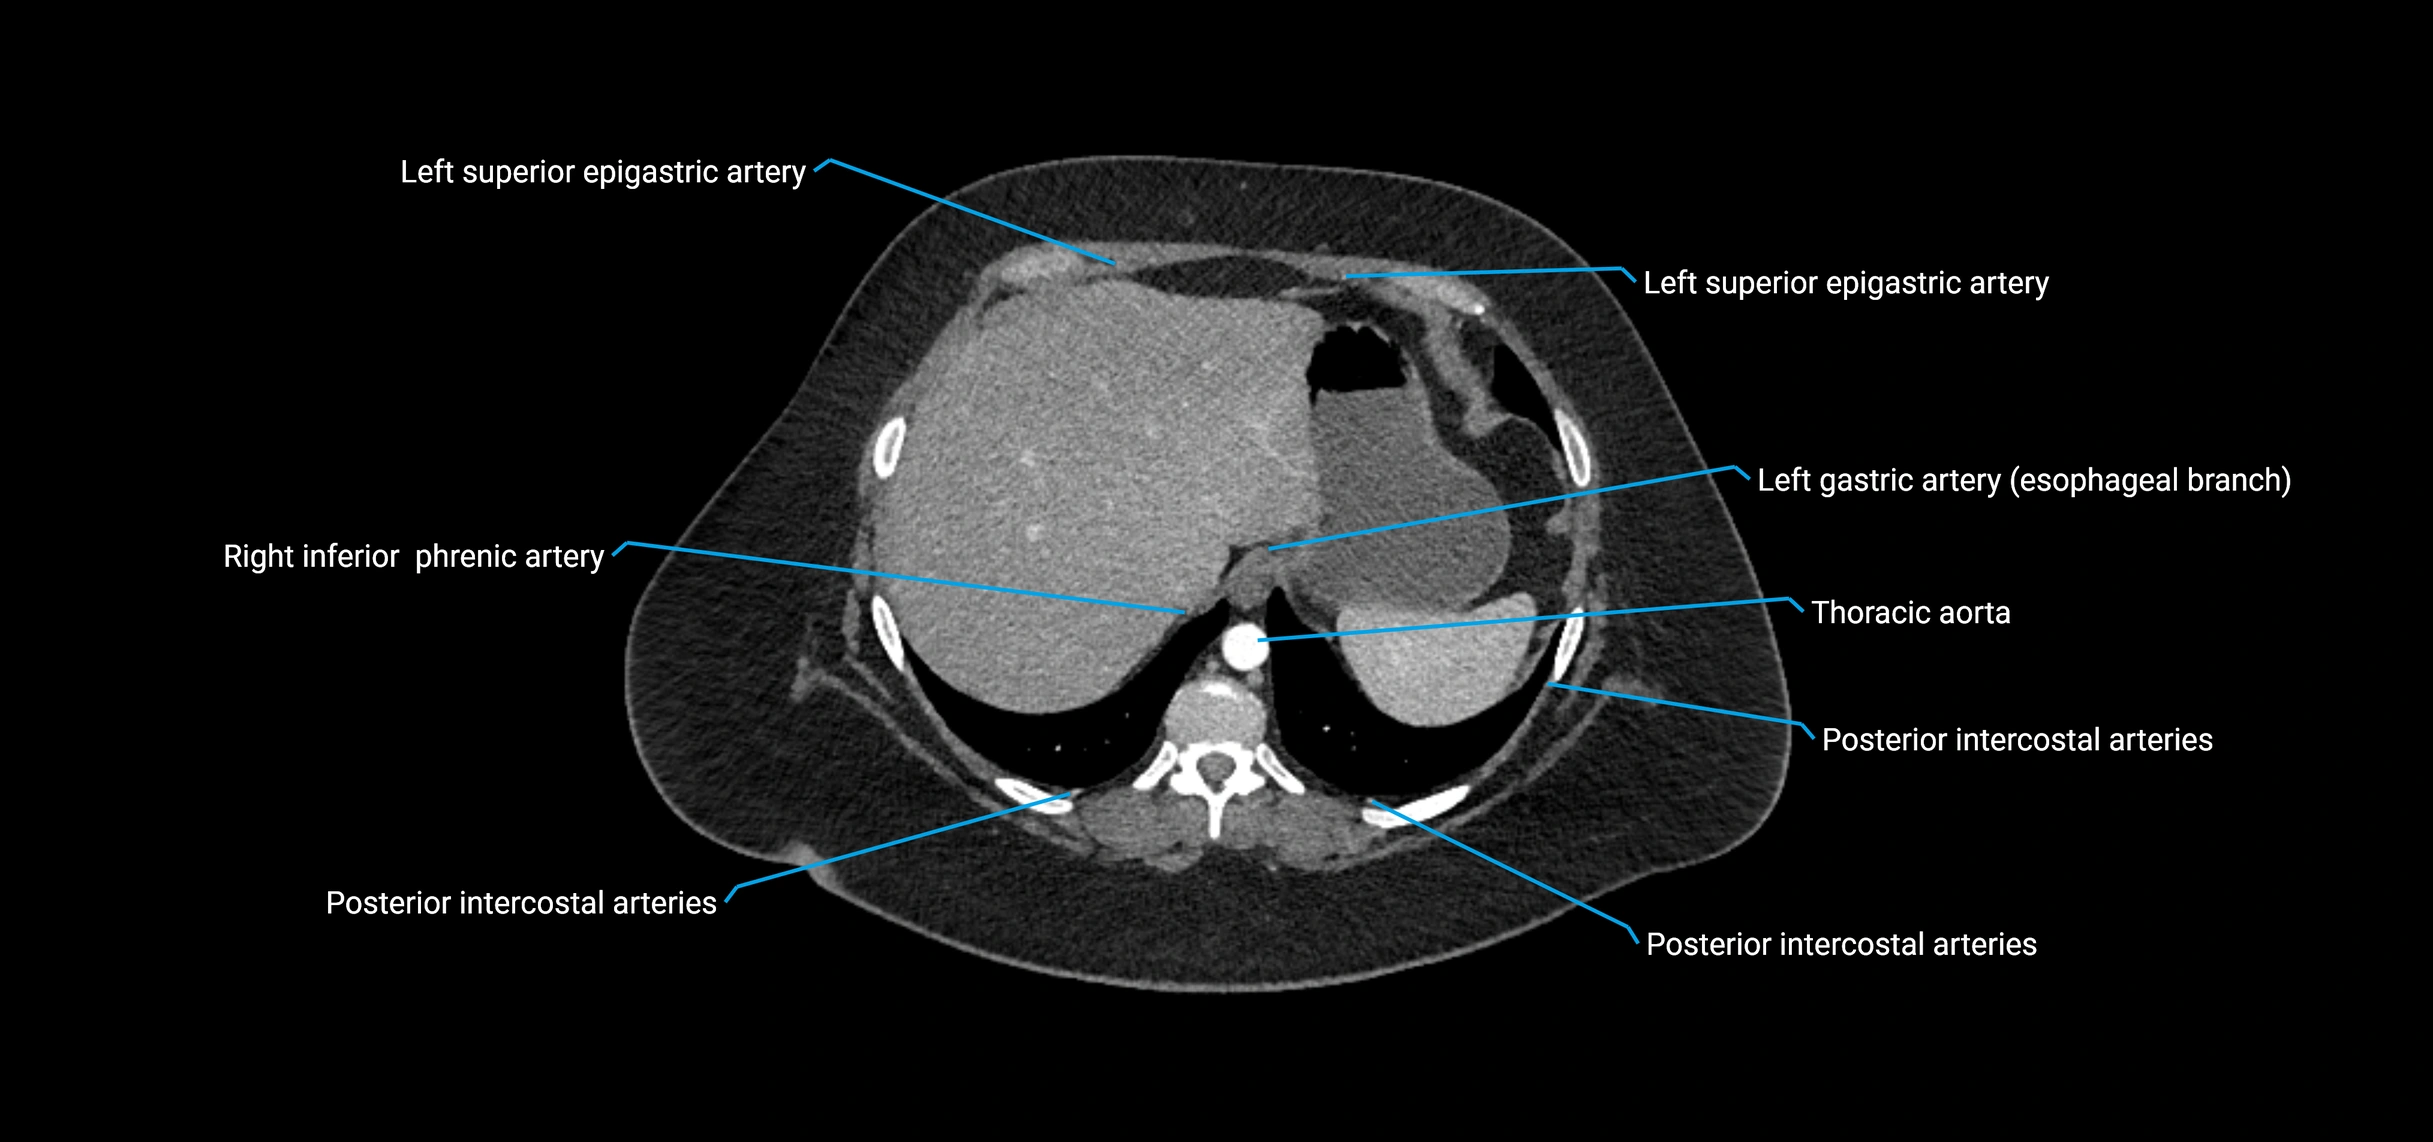

Contrast-enhanced CT (CTA):

• Gold standard for abdominal aortic imaging

• Provides excellent detail of lumen, wall, aneurysm, thrombus, and branch vessels

• Multiplanar and 3D reconstructions help in aneurysm measurement, stent graft planning, and dissection evaluation